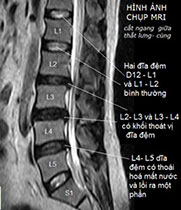

Thoát vị đĩa đệm L4-L5, L5-S1, chèn ép rễ thần kinh Thoát vị đĩa đệm L4-L5 ra sau #5mm, chèn ép bao màng cứng, gây hẹp lỗ liên hợp hai bên, chèn ép rễ thần kinh L4, L5. Thoát vị đĩa đệm L5-S1 trung tâm ra sau #5mm, chèn ép mặt trước bao màng cứng, gây hẹp lỗ liên hợp hai bên, chèn ép rễ thần kinh L5, S1.❮ đọc tiếp ❯